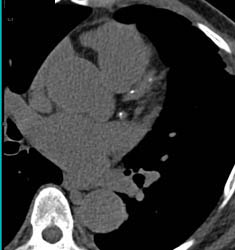

Nice View of Sa Nodal Branches Off RCA